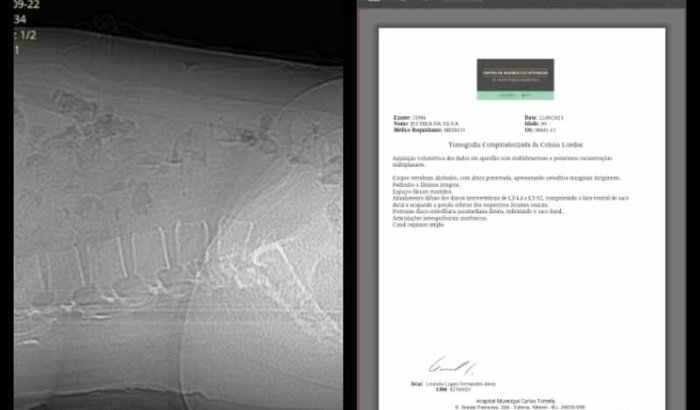

Olá, me chamo Jucinea e estou precisando com urgência fazer essa Cirurgia Hérnia de Disco na Lombar, no momento estou desempregada e sentido muita dor, essas doações além da cirurgia, seria para pós operatório ( medicamentos e etc...). Sou ver tudo

Olá, me chamo Jucinea e estou precisando com urgência fazer essa Cirurgia Hérnia de Disco na Lombar, no momento estou desempregada e sentido muita dor, essas doações além da cirurgia, seria para pós operatório ( medicamentos e etc...). Sou de Niterói-Fonseca RJ e fico agradecida desde já pelas ajudas. 4205136@vakinha.com.br